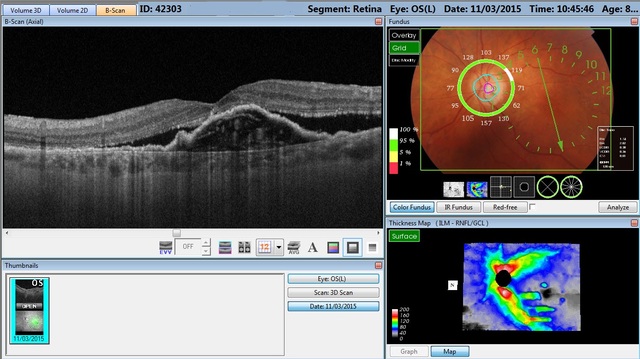

La dimensión OCT a su alcance: simplemente toque la pantalla de operaciones y Maestro automáticamente escaneará ambos ojos y efectuará simultáneamente un análisis OCT y una imagen de fondo ocular en color real, un proceso rápido y preciso. Maestro, gracias a su campo amplio 12mm x 9mm, junto con la detección de 7 capas de segmentación automática, proporciona mediciones y topografías del nervio óptico y mácula con un único escaneo.

También produce B-Scans de alta definición a una velocidad de 50.000 A-Scans por segundo. El equipo ofrece, además, una combinación exclusiva y simultánea de OCT e imágenes de fondo de ojo, simplemente con su función de activación. La imagen de retina es una imagen de fondo de ojo en color real que proporciona detalles con una nitidez inigualable. Asimismo, captura imágenes verde aneritra. Ofrece una amplia selección de funciones de análisis (análisis del disco óptico, mácula en 3D y escaneo amplio de 12mm en 3D, entre otros).  Reporte HOOD de Glaucoma (Grosor retinal/RNFL/GCL y Nervio Óptico). OCT-Angiografía.

• Scan de OCT de campo amplio de 12mm x 9mm que suministra medición y topografía del nervio óptico y de la mácula en un solo scan.

• Numerosas funciones de análisis: Análisis de la papila o disco óptico, análisis de la mácula en 3D, scan en 3D de 12mm de ancho, y más.

• Reporte HOOD diseñado para Glaucoma (Grosor retinal/RNFL/GCL y Nervio óptico) que relaciona el daño estructural y funcional de la retina.